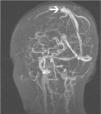

Una niña de 12 años de edad, sin antecedentes patológicos de interés es diagnosticada de disgerminoma supraselar por un cuadro de panhipopituitarismo. Fue sometida a una resección transesfenoidal parcial y posteriormente comenzó con un tratamiento quimioterápico, de cisplatino, etopóxido y bleomicina. Una semana después de recibir el primer ciclo, inicia un cuadro progresivo de cefalea holocraneal intensa que interfiere con el sueño, junto con náuseas, visión borrosa y dificultad para mover las extremidades izquierdas. En la exploración neurológica se observaron una hemiparesia izquierda leve (síndrome faciobraquiocrural) y un papiledema bilateral en la exploración del fondo de ojo. Se practicó una tomografía computarizada (TC) craneal que fue normal y se procedió al ingreso de la paciente. En las horas siguientes sufrió una progresión del cuadro con aparición de tetraparesia de predominio izquierdo y crisis parciales motoras con generalización secundaria, por lo que se decidió su ingreso en la unidad de cuidados intensivos pediátricos. Se practicó una resonancia magnética (RM) craneal con secuencias de angiorresonancia (2DTOF) que demostró la existencia de áreas de restricción de la difusión en región motora cortical bilateral, imagen compatible con un infarto venoso cortical derecho y una trombosis de los senos longitudinal, sigmoide y transverso derechos, así como del seno transverso izquierdo (figs. 1 y 2). El resto de estudios complementarios fueron normales. Las crisis fueron controladas con anticonvulsionantes y la paciente fue tratada con medicación anticoagulante durante 3 meses. En el momento del alta no se apreciaron secuelas neurológicas en ninguna localización y durante el año de seguimiento posterior la paciente ha permanecido asintomática. Las RM de control realizadas a los 3 y a los 6 meses fueron normales.